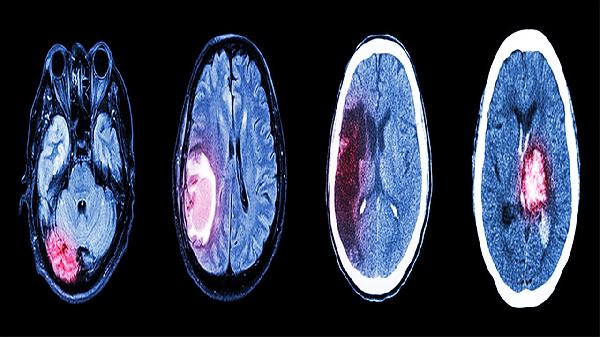

理解能力提升需要多维度协同干预。饮食中增加蓝莓、黑巧克力等黄酮类物质摄入,配合太极拳等协调性运动增强大脑双侧整合。建立错题本系统记录思维卡点,定期进行瑞文推理测验评估进步。注意避免长时间碳水化合物过量摄入导致的餐后困倦,保持适度饥饿感能提升脑源性神经营养因子活性。当伴随持续头痛或记忆力骤降时,需神经内科就诊排除器质性疾病。